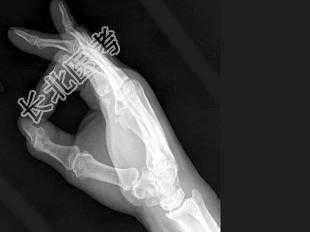

- 单项选择题男,24岁, 双手疼痛,结合图像, 最可能的诊断是 ( )

A、肢端肥大症

B、骨质疏松症

C、类风湿关节炎

D、痛风

E、维生素D缺乏症